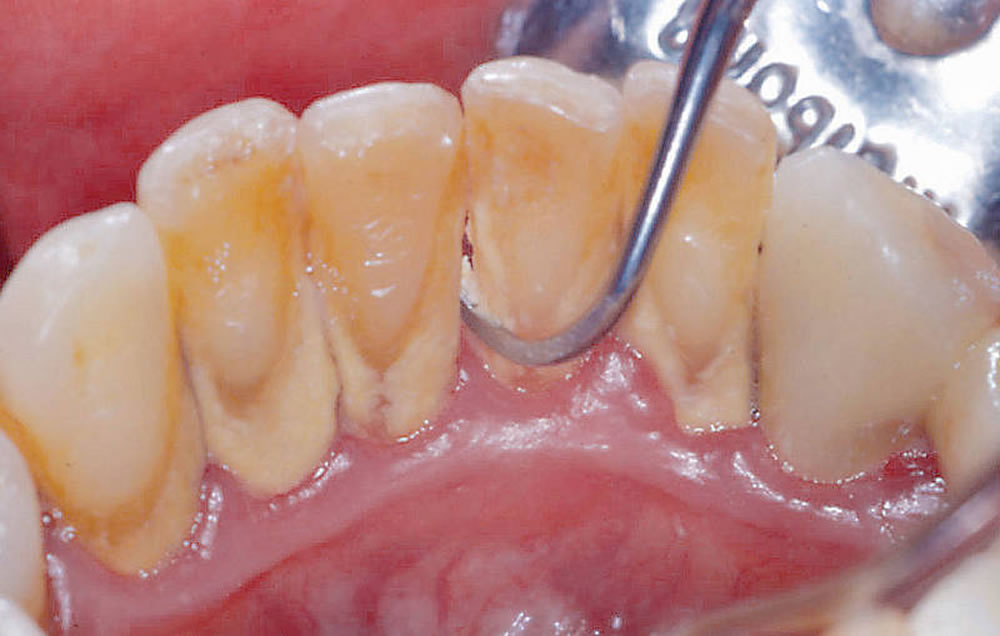

スケーラーというのは歯垢や歯石を除去するための専用の歯科道具であり、これは「超音波式スケーラー」と「手動式スケーラー」とに分けられます。

前者は短い時間で広範囲の汚れを落とせますが、精度という点ではやや劣ります。後者は細かいところまで綺麗にできますが、手間暇と時間が掛かります。当院ではこの2種類のスケーラーを使い分けることで、効率的かつ効果的な治療を行います。以下、スケーラーの特徴を挙げます。

手動式ハンドスケーラー

手動で歯垢、歯石を取り除く道具で、時間は掛かるものの歯の細かい部分まで汚れを落とすことができます。